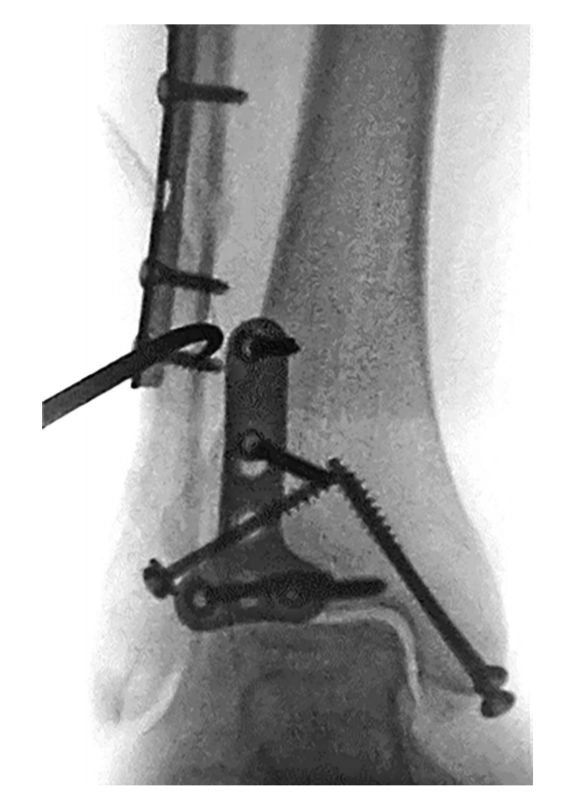

④ 固定后踝后,经同一后外侧切口固定外踝,通常建议采用后侧钢板固定,如腓骨骨折线过高,则重新切口外侧钢板固定腓骨。

⑧ 复位后典型病例示意图。